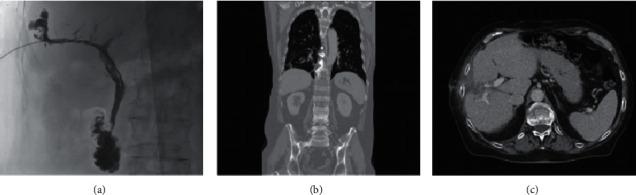

Microwave ablation is a safe and effective interventional approach, widely used in the treatment of unresectable primary or metastatic hepatic lesions. Thoracobiliary fistula is a rare postablation complication that can be treated with a conservative or surgical approach. We reviewed aetiology, pathogenesis, clinical picture, diagnostic possibilities, and therapeutic options for biliothoracic fistula developed after microwave ablation of liver metastasis. Furthermore, we reported our experience of successful conservative management of a nonhealing thoracobiliary fistula occurred after percutaneous thermal ablation of colorectal cancer liver metastasis. Our case supports a conservative approach based on percutaneous biliary system decompression and synthetic glue embolization for the treatment of combined biliopleural and biliobronchial fistula.

微波消融是一种安全有效的介入方法,广泛应用于不可切除的原发性或转移性肝病灶的治疗。胸胆瘘是一种罕见的消融后并发症,可采用保守或手术方法治疗。我们回顾了肝转移瘤微波消融术后发生胆胸瘘的病因、发病机制、临床表现、诊断方法及治疗选择。此外,我们报告了经皮热消融结直肠癌肝转移后发生的不愈合胸胆瘘成功保守治疗的经验。我们的病例支持基于经皮胆道系统减压和合成胶水栓塞的保守方法来治疗合并的胆胸膜瘘和胆支气管瘘。